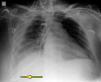

Mujer de 46 años, que ingresó en la UCI por hemorragia subaracnoidea. Como parte del tratamiento habitual, se decidió iniciar tratamiento con nutrición enteral (NE) por sonda nasogástrica (SNG). Se insertó la SNG según refieren sin incidencias. Se realizó Rx de tórax de control y se trasladó la enferma a radiología para realizar una TC toraco-abdominal programada. Al valorar los estudios se apreció en la Rx de tórax el extremo distal de la SNG en cavidad pleural derecha (fig. 1, flecha) que se confirmó con las imágenes de la TC como hallazgo incidental (fig. 2, flechas). Es importante resaltar la necesidad de realizar, antes de iniciar la NE, una Rx de tórax o un control ecográfico, para comprobar la localización del extremo distal en todo paciente al que se le coloca una SNG para nutrición. El no hacerlo puede producir serias complicaciones mecánicas.